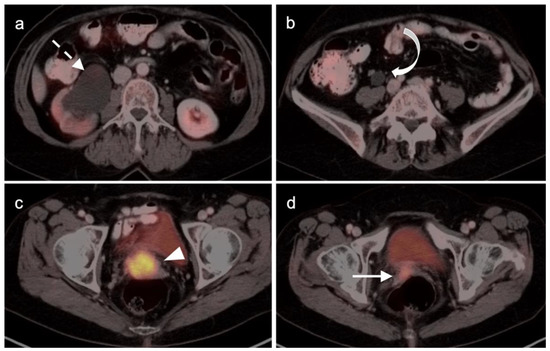

2.3.1. Endometrial Carcinoma